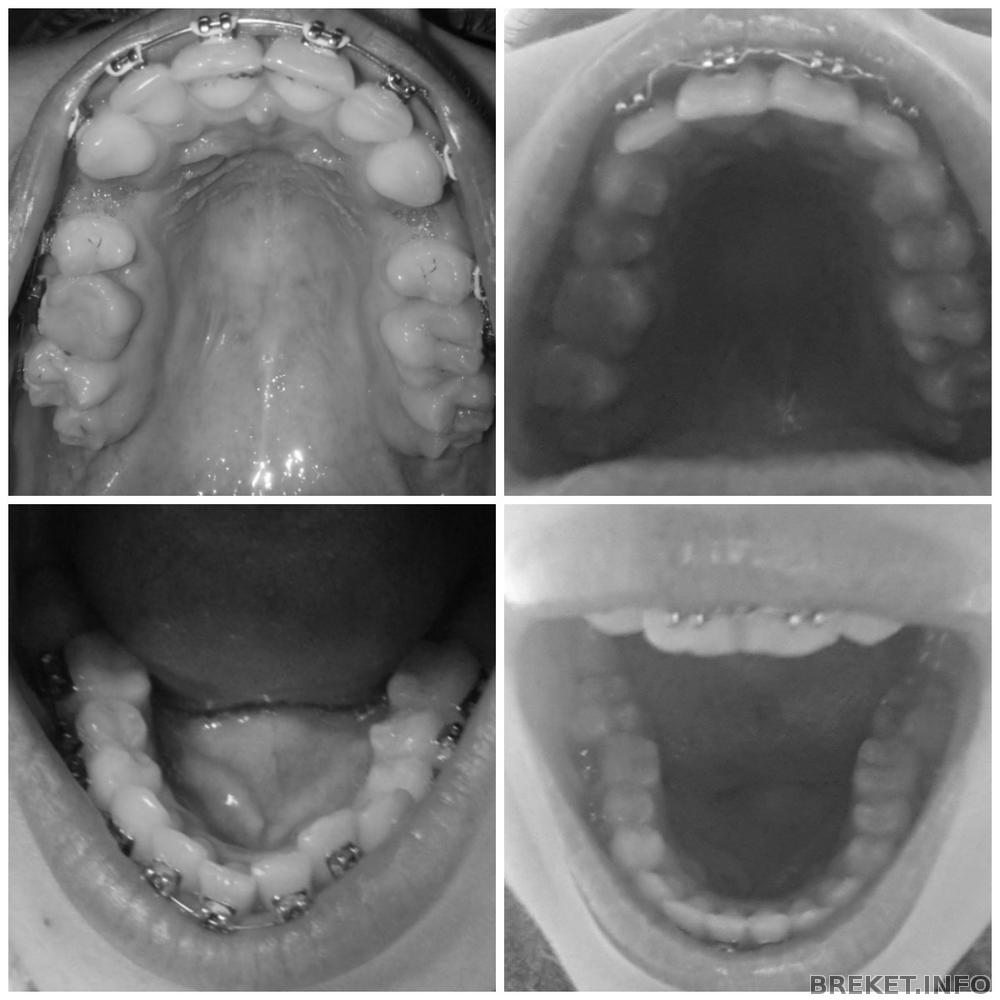

RaiseHopes, Да, уж.., посмотрела я на вашу нижнюю челюсть. У вас тоже беда. Такое ощущение будто челюсть узкая, а потом БАЦ и семерки широко стоят. Вот не хочу я такого. Мне мой орт тоже сказала, ну если я ооооочень хочу, то она мне поставит, но я буду жалеть, если подключу семерки, что это болезненное все и чистить проблематично. Но такая картина как у вас, меня бы точно не устроила.

Хотя у вас хоть шестерки не завалены. У меня они явно в бок. На счет центра - про микроимплант не слышала, вроде как-то проще его двигают.

Varechka, в идеале, как я себе представляла, что 6ки все-таки должны стоять ровно. Вот даже посмотреть на продемонстрированном коллаже от RaiseHopes. Там с семерками беда, но шестерки внизу хорошо стоят. А у меня вообще нет ровной "подковы". Про центр - конечно, если ровнять верх, то и низ, так как они в тандеме.

shelkovaya01@mail.ru, у вас еще все более-менее) думала, что катастрофа, а как фото посмотрела- не так уж и плохо. У меня с этим вообще беда. Шестерки на НЧ очень съехали внутрь, семерки на ВЧ развернуты в сторону щек так, что они мне реально мешают. Спрашивала орта нормально ли это, т.к. брекеты тоже до шестерок стоят, он сказал - конечно не нормально. Правда потом пару раз пришлось напоминать. Договорились с ним: я удаляю все восьмерки и начинаем доклеивать замки на 7ые. Решили снизу начнем. Но вышло по-другому, он посмотрел и начал с ВЧ. Час клеил, еле-еле, постоянно замки срывались, настолько сильно семерки развернуты. Дугу вставлял- опять слетали. С горем пополам таки приклеил замки на 7ки) поставил дугу слабее, чтоб опять не отпали, еле выгнул ее как надо. Вообщем, очень сложно было. Но все возможно))